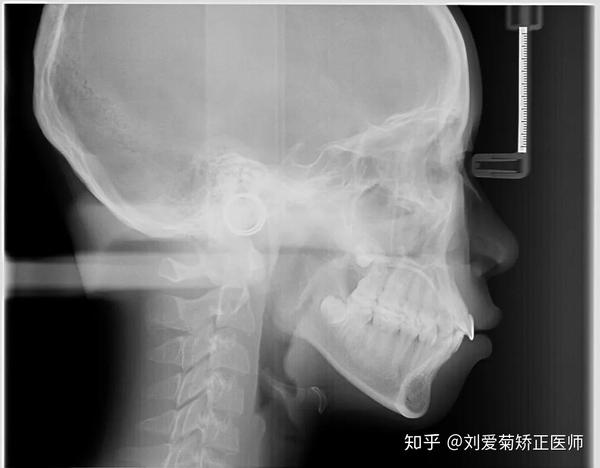

侧位的x光片可以告诉我们上下颚骨的相对的关系,牙齿的走向,判断暴牙